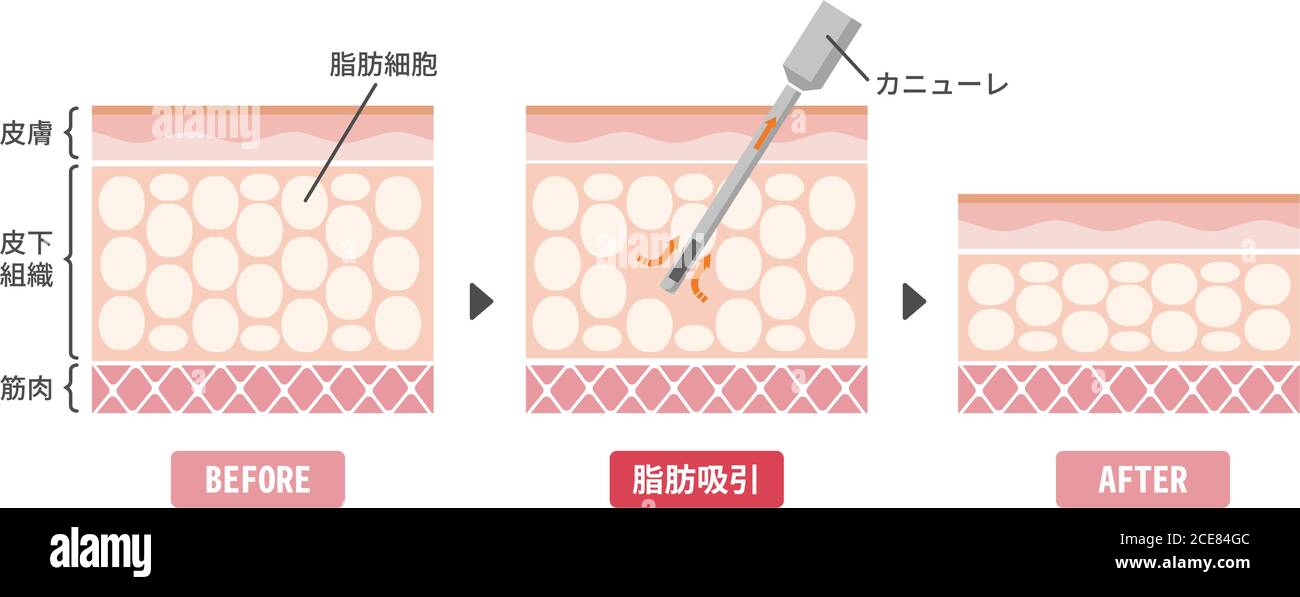

Illustration vectorielle du processus de liposuccion / vue en coupe de la peau Illustration de Vecteurhttps://www.alamyimages.fr/image-license-details/?v=1https://www.alamyimages.fr/illustration-vectorielle-du-processus-de-liposuccion-vue-en-coupe-de-la-peau-image370202117.html

Illustration vectorielle du processus de liposuccion / vue en coupe de la peau Illustration de Vecteurhttps://www.alamyimages.fr/image-license-details/?v=1https://www.alamyimages.fr/illustration-vectorielle-du-processus-de-liposuccion-vue-en-coupe-de-la-peau-image370202117.htmlRF2CE84G5–Illustration vectorielle du processus de liposuccion / vue en coupe de la peau

Illustration vectorielle du processus de liposuccion / vue en coupe de la peau Illustration de Vecteurhttps://www.alamyimages.fr/image-license-details/?v=1https://www.alamyimages.fr/illustration-vectorielle-du-processus-de-liposuccion-vue-en-coupe-de-la-peau-image370202124.html

Illustration vectorielle du processus de liposuccion / vue en coupe de la peau Illustration de Vecteurhttps://www.alamyimages.fr/image-license-details/?v=1https://www.alamyimages.fr/illustration-vectorielle-du-processus-de-liposuccion-vue-en-coupe-de-la-peau-image370202124.htmlRF2CE84GC–Illustration vectorielle du processus de liposuccion / vue en coupe de la peau